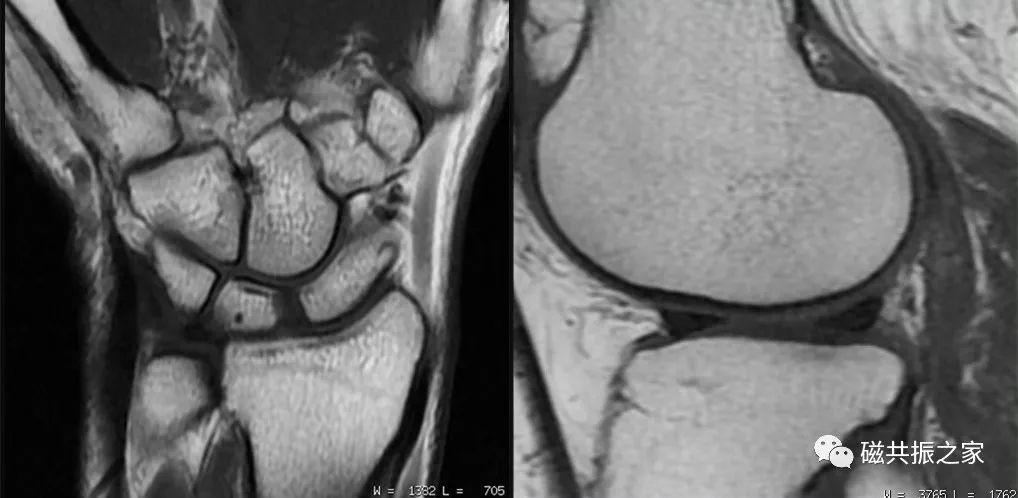

MRI具有多参数、多方位和优异的软组织对比度等特点,其在四肢关节的影像学检查中得到了极其广泛的应用;同时,MRI多序列组合可获得多种对比图像,为四肢关节疾病的诊断与评估提供了更为丰富的影像学信息。但MRI图像质量受到诸多因素的影响,那么在实际的临床扫描中应如何做好四肢关节的MRI扫描?本期主要分享一些四肢关节的MRI成像要点。

多序列组合是MRI最大的优势,同时也是解决临床问题的关键。MRI的序列众多,各序列都有各自的优缺点,在四肢关节的扫描时,应在规范化扫描的基础上做的个性化的扫描,借助于各序列的临床优势,合理地优化序列组合,才能为临床诊疗提供更为有利的、精准的影像学信息。

如T1WI较其它序列使用较短的扫描时间即可获得更高的信噪比图像。在四肢关节的扫描中建议T1WI使用较大的矩阵(更小的体素)扫描,以获得更高的图像分辨率。高分辨率的图像不但可以显示更为精细的解剖结构,还能为临床诊疗提供更多的影像学信息。在时间和信噪比都能保证的情况下,对于四肢关节的扫描应尽量采用小的体素扫描,以提高图像的分辨率。

四肢关节的扫描常扫描1-2个方位的T1WI,在实际的临床扫描中建议使用较大的矩阵扫描,以提高图像的分辨率。

再如,在四肢关节的扫描时为了使得组织对比更为丰富,更好的评估关节软骨病变等,通常会采用TE为30-50ms的序列扫描,该中间权重的TE值不但可以保证足够的信噪比和对比度,还能使关节软骨的信号更亮,更有利我们对其病变的评估。